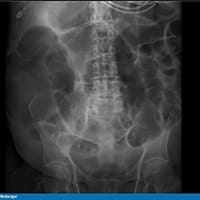

Todos os outros exames laboratoriais estão normais. É feita uma radiografia de abdome. O paciente é internado por causa dos seus exames. Uma tomografia computadorizada (TC) de abdome e pelve sem contraste é feita na sequência. Os achados dos exames de imagem são mostrados abaixo (Figuras 1 a 4).